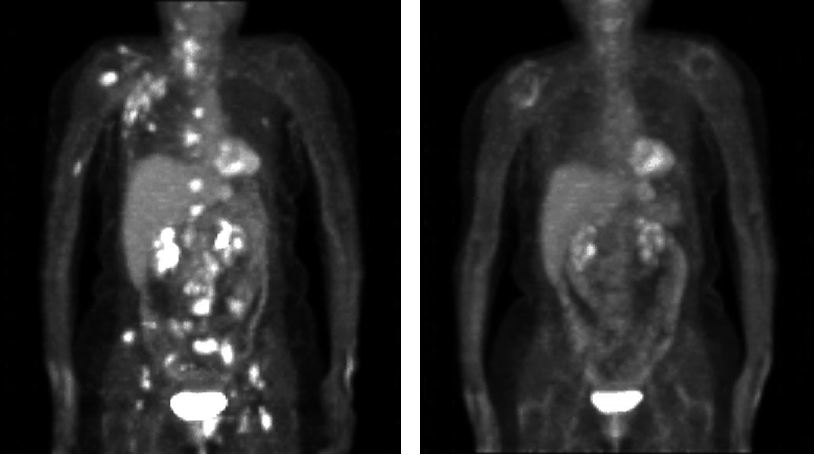

BN ung thư vú có di căn hạch nách phải

PET/CT K vú di căn xương,hạch nách